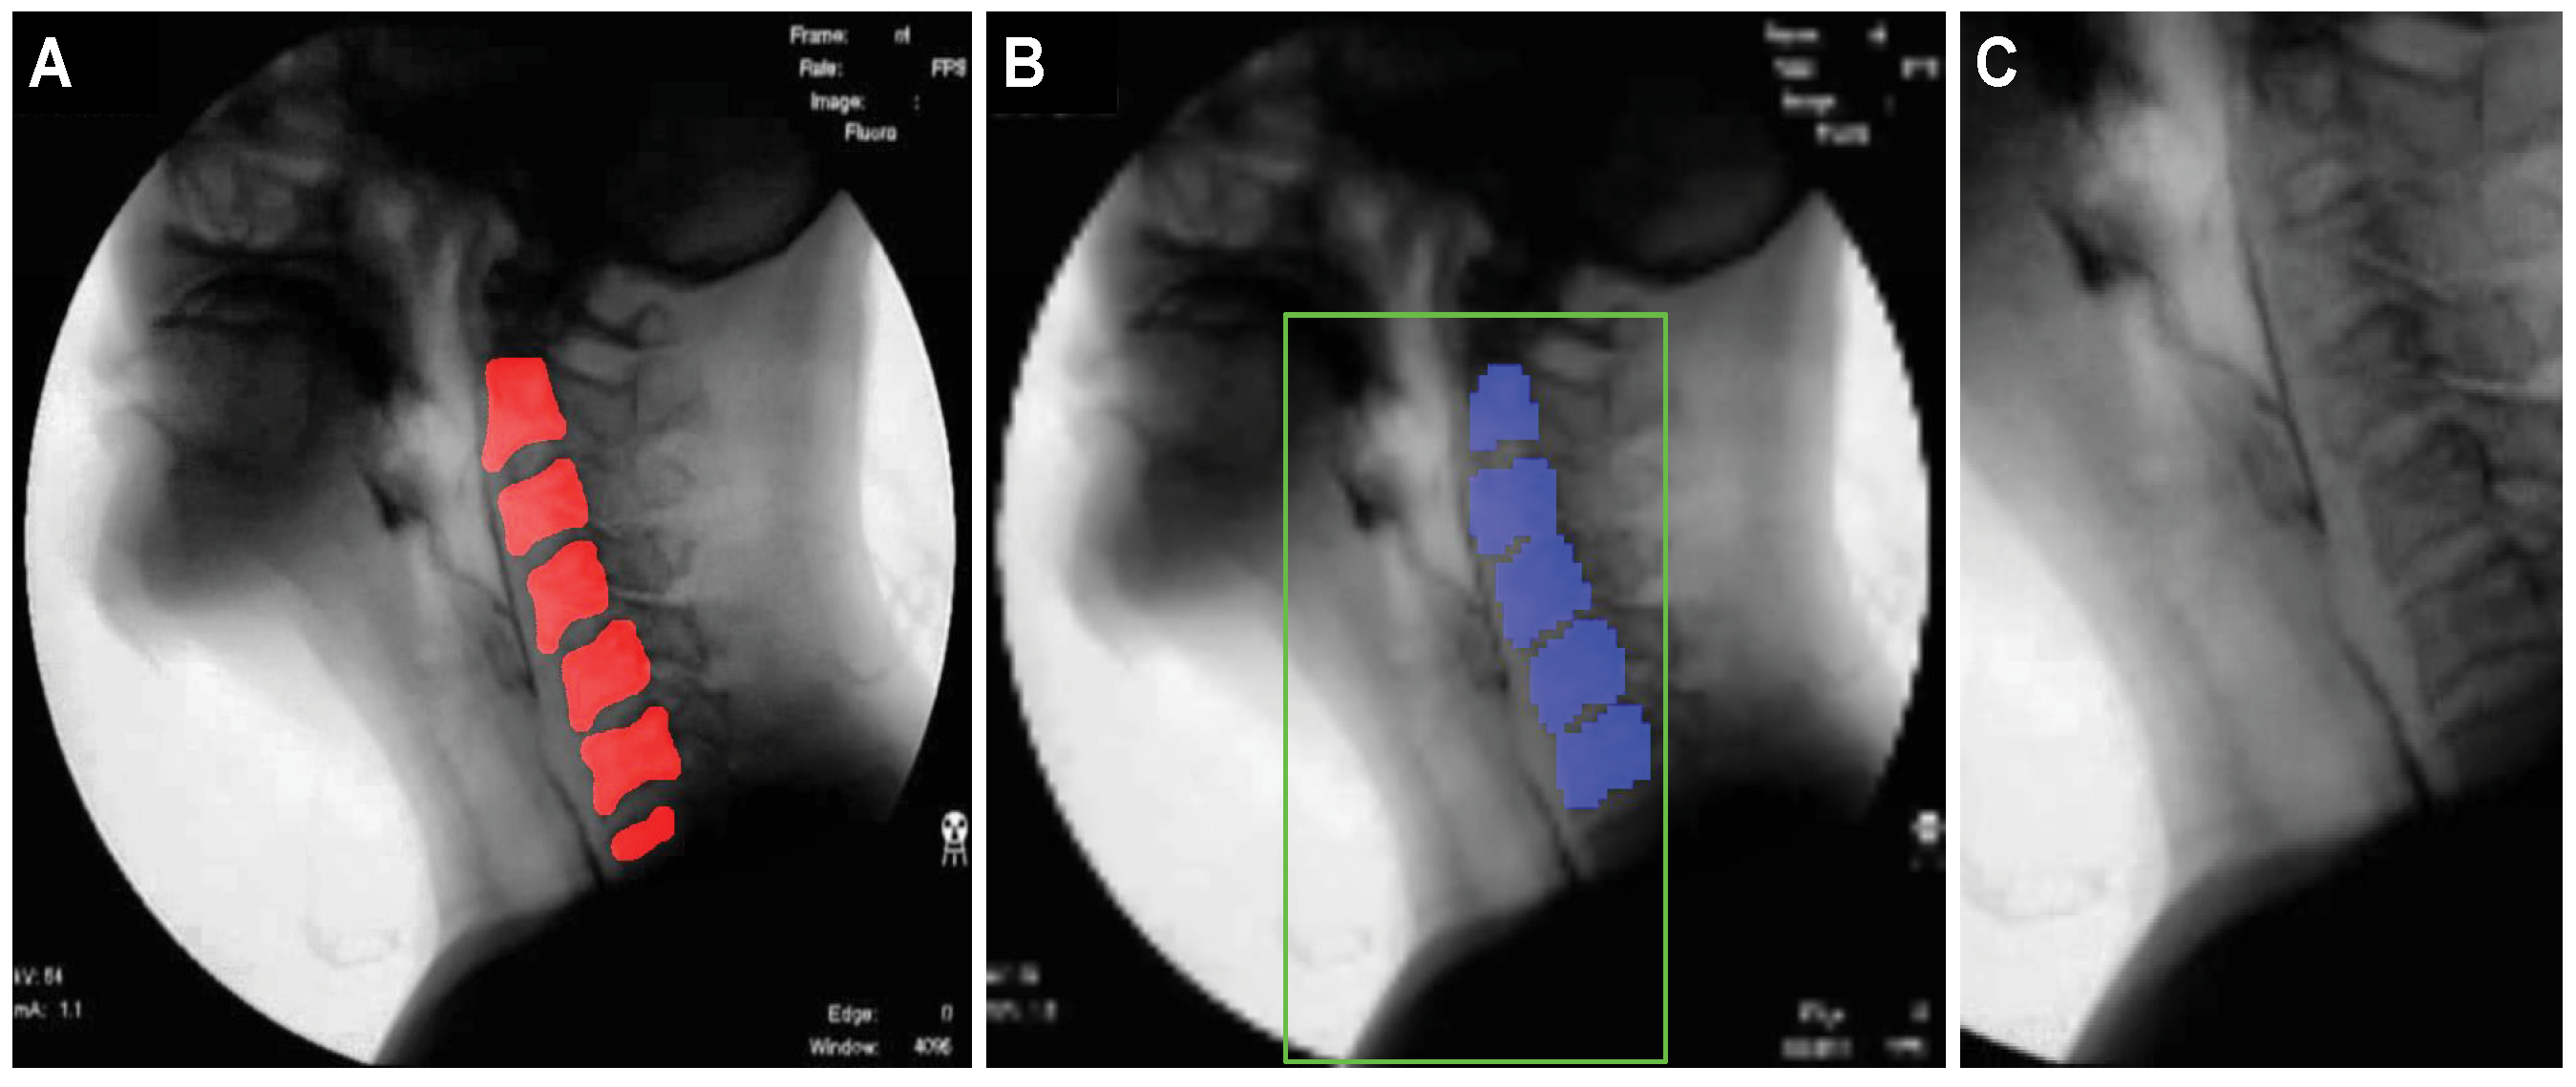

2.3.1. Creation of a Dynamic ROI Using Global Localization of the Cervical Spinal Column